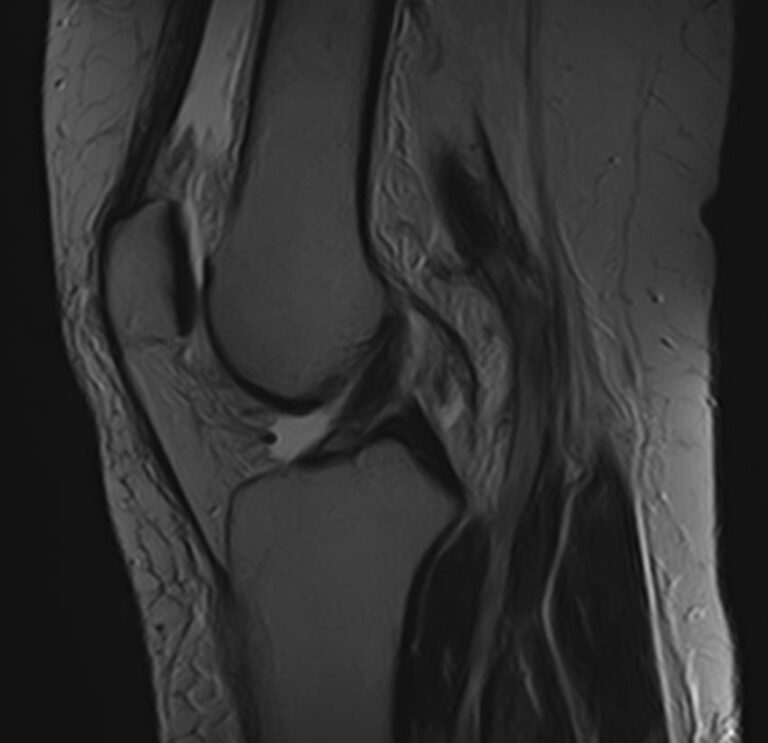

Магнитно-резонансная томография является высокоинформативным методом выявления причин возникновения заболеваний коленного сустава. В клинике «Доступная медицина» диагностика осуществляется на новейшем высокопольном томографе закрытого типа TOSHIBA VANTAGE TITAN 1,5 Тесла, обеспечивающем высочайшее качество изображений исследуемой зоны.

Томограф позволяет детально визуализировать как костные структуры колена, так и окружающие мягкие ткани данной анатомической области, включая мышцы, связки, нервные сплетение, сосуды.